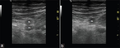

Compression of the popliteal vein. Notice the anterior location of the vein. Normal exam.

| current | 17:02, 1 November 2015 | 512 × 203 (83 KB) | Neil.m.young (Talk | contribs) | Compression of the popliteal vein. Notice the anterior location of the vein. Normal exam. |